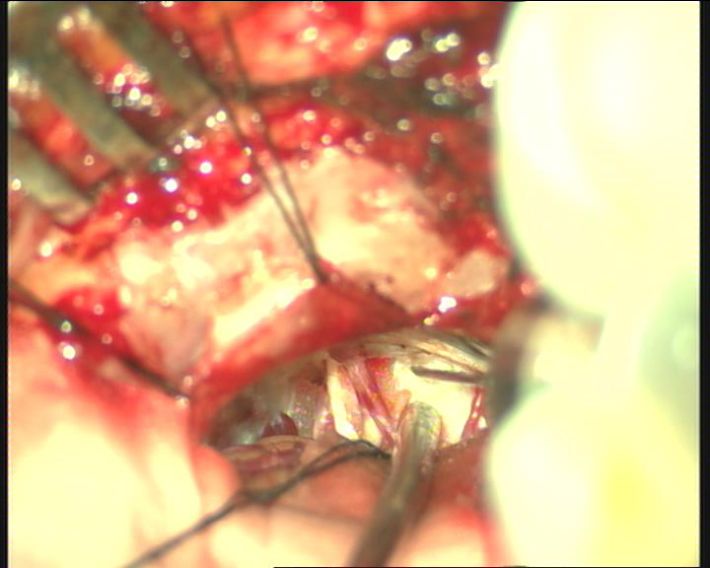

术中证实我们对影像结果的判断,迂曲的椎动脉同时压迫面神经及三叉神经,面神经受压变形,三叉神经被压向天幕呈薄片状,尝试多点推开椎动脉,但对面神经仍有向后压迫,无法实施“多点架桥”,故选择“生物胶悬吊”。

迂曲的椎动脉压迫面神经,面神经受压变形。

迂曲的椎动脉压迫三叉神经,推开椎动脉可见三叉神经被压向天幕呈薄片状。

于三叉神经与椎动脉之间临时置入明胶海棉,使椎动脉远离三叉神经,再于椎动脉与脑干之间置入明胶海绵,使椎动脉远离面神经及脑干,使椎动脉临时固定。

进一步应用生物胶将椎动脉悬吊固定。